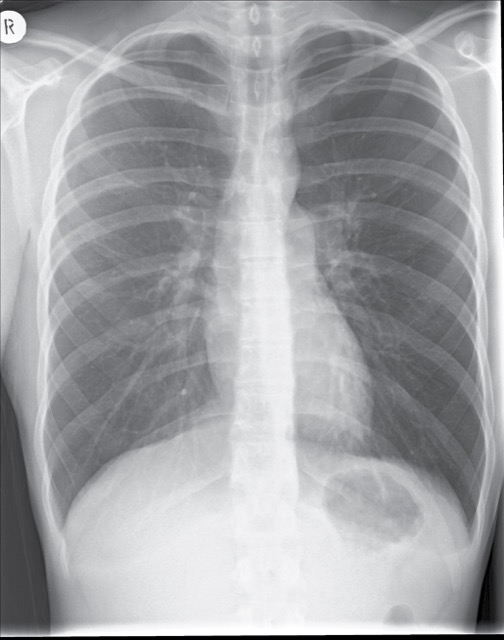

A 65-year-old smoker presents with acute dyspnoea. Chest X-ray shows a visible pleural line with absent lung markings laterally.

Bilateral pleural effusion — 72-year-old with cardiac failure

Right lower lobe consolidation — 58-year-old with productive cough

Widened mediastinum — 45-year-old with tearing chest pain